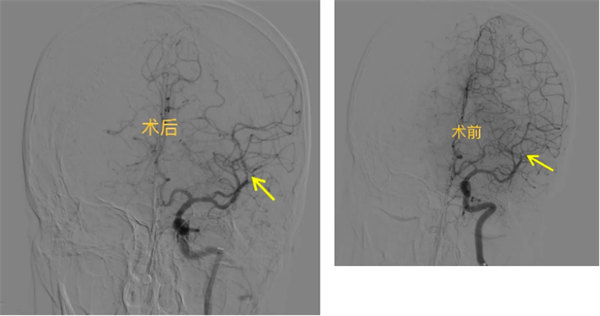

席聰考慮有急診腦動(dòng)脈介入取栓指征,并告知王先生家屬介入取栓的必要性及風(fēng)險(xiǎn),該病為顱內(nèi)大動(dòng)脈閉塞,危險(xiǎn)性極高,此時(shí)萬分危急,每晚一分鐘治療患者的預(yù)后越差,可能終身殘疾甚至有生命危險(xiǎn),且王先生的癥狀還在波動(dòng),出現(xiàn)了不能講話的情況,王先生家屬?zèng)Q定采用取栓治療,在主任席聰、副主任醫(yī)師關(guān)建兵等介入團(tuán)隊(duì)高效配合下,不到1小時(shí),便開通了王先生左側(cè)大腦中動(dòng)脈急性閉塞血管。術(shù)后,患者失語癥狀即刻完全好轉(zhuǎn),NHISS評(píng)分4分。